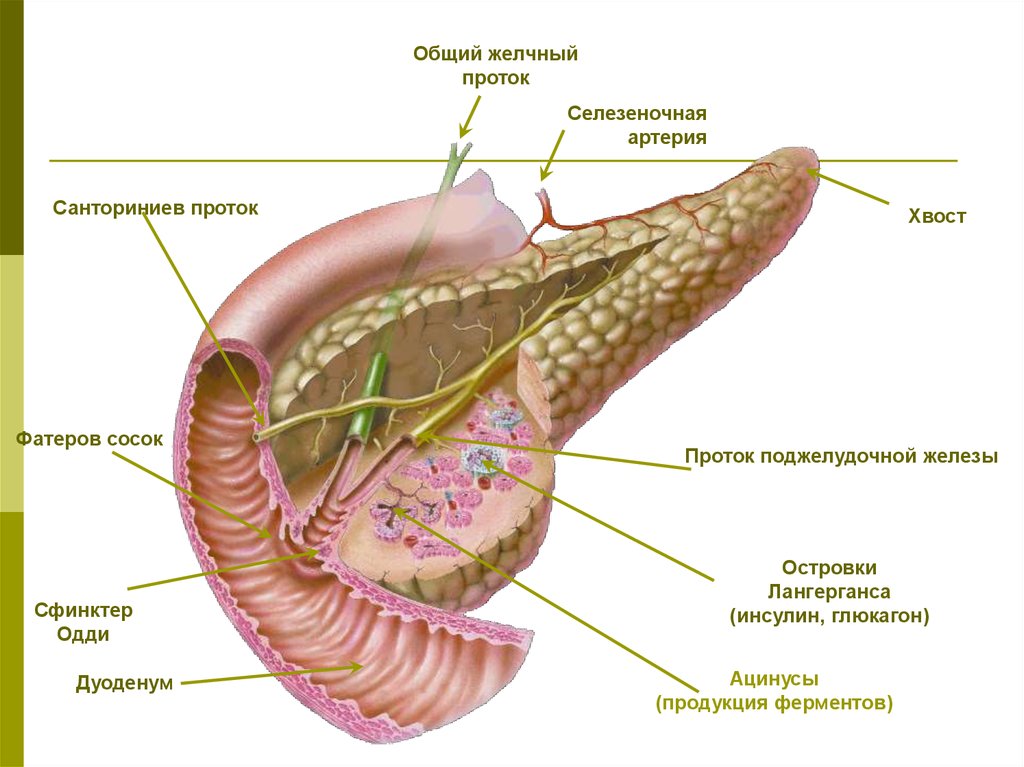

Анатомия и особенности Гартманова кармана желчного пузыря